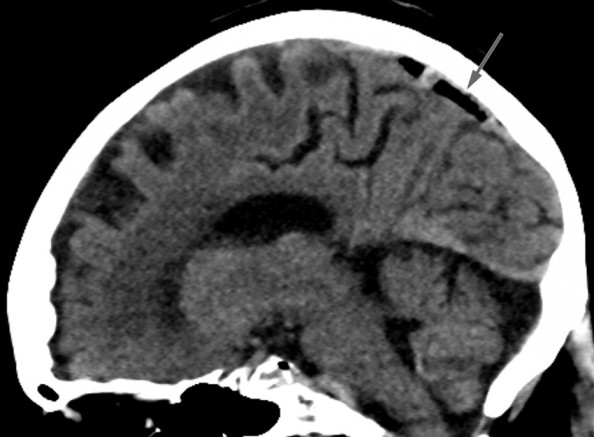

Bildet viser luft i sinus sagittalis superior, et tilfeldig funn hos en kvinne i 80-årene undersøkt med CT caput ett døgn etter fall i hjemmet med hodetraume og forbigående bevissthetstap. CT viste ingen tegn til intrakranial blødning eller skjelettskade, men det var luft i cerebrale venesinuser, mest i sinus sagittalis superior, mindre luftbobler i sinus transversus bilateralt, høyre sinus sigmoideus, sinus cavernosus og i en vene kranialt i venstre orbita. Grunnet rask atrieflimmer hadde pasienten før CT fått anlagt perifert venekateter på høyre underarm med injeksjon av to doser med 5 mg metoprolol. Pasienten hadde ingen symptomer som kunne tilskrives cerebral venøs luftembolisme.